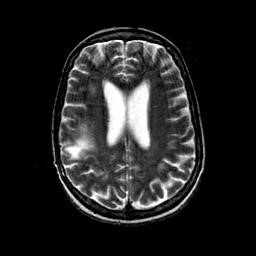

На Т2-зависимых томограммах в белом веществе обнаруживаются:

- диффузные поля гиперинтенсивного сигнала без четких границ, одно- или двухсторонние;

- либо очаги 1-3 см в диаметре.

Типично расположение очагов воспаления в валике мозолистого тела. Дифференциальную диагностику необходимо выполнять с прогрессирующей мультифокальной лейкоэнцефалопатией и лимфомой.

При МРТ картина ПМЛ типичная:

- выявляются несимметричные участки высокого сигнала на Т2-зависимых томограммах, преимущественно, в теменных и затылочных долях;

- поражение распространяются до подкорковых зон;

- масс-эффекта нет;

- контрастирование бывает редко, с быстрым увеличением и слиянием очагов.